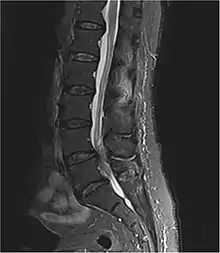

Diagnostic method | Medical imaging (MRI, CT scan)[1][3] |

Diagnosis is first suspected clinically based on history and physical exam and usually confirmed by an MRI scan or CT scan, depending on availability.[4] Bladder scanning and loss of catheter sensation can also be used to evaluate bladder dysfunction in suspected cases of cauda equina syndrome and can aid diagnosis before MRI scanning. Early surgery in acute onset of severe cases has been reported to be important.[4]